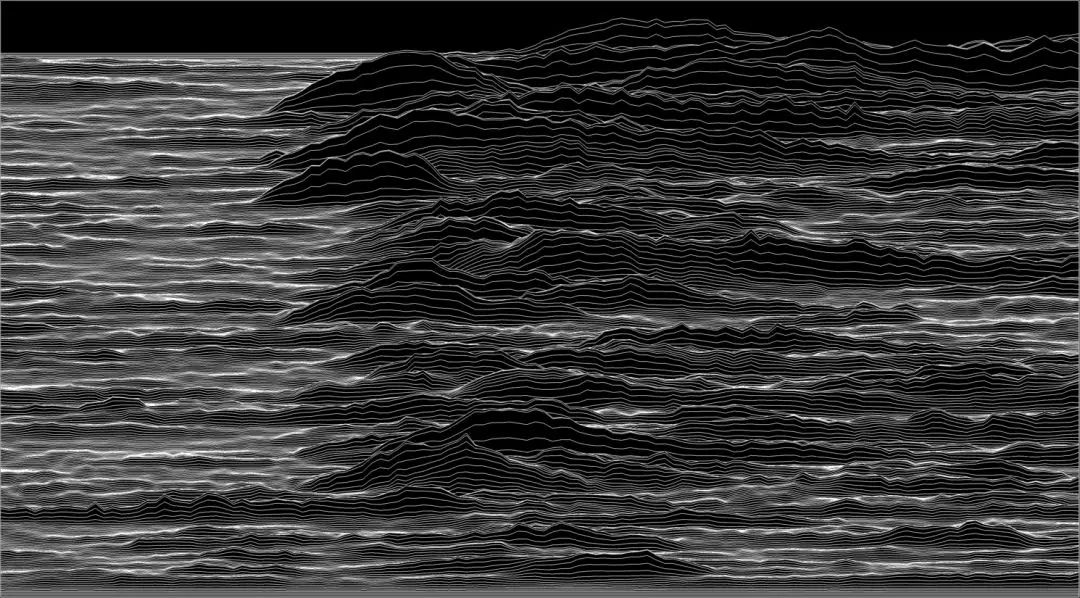

2018 年荣誉奖作品:《维持复杂生命的复杂节奏》

Complex Rhythm Sustaining Complex Life

科学艺术家:Yishul Wei(荷兰神经科学研究所)

心律是一项基本的生命体征,它与我们的身体状况、活动、情感和感受有关,即使在人睡着之后,心率仍表现出可变性,这是由自主神经系统每天 24 小时的不间断调节所带来的。

这张图显示了入睡后的健康成人的心电图(ECG),连续记录了 15 分钟。连续等长的片段对应着平均心率,彼此叠加。

很明显可以看出,心脏节律不完全是周期性的,否则心跳(心电图中的R波或“尖峰”)会重叠,但也不是随机的,具有复杂结构,反映了我们意识之外潜在的复杂非线性神经控制。